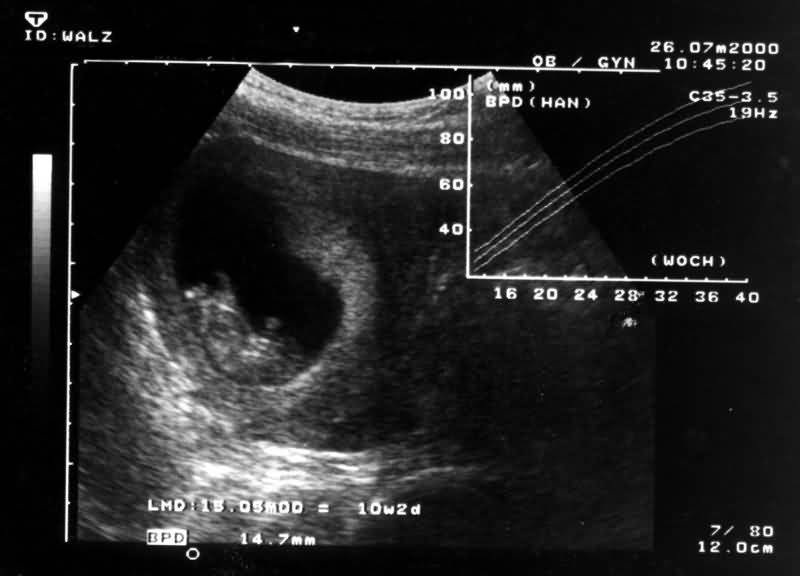

26. Juli 2000

zurück  Ultraschallbilder  weiter